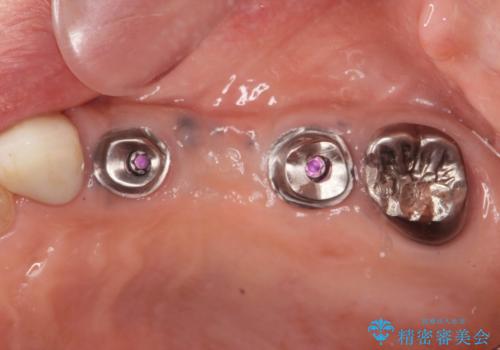

複数の奥歯の欠損 インプラントによる咬合機能回復

- 105.6万円(インプラント×2・チタンカスタムアバットメント×2・ジルコニアクラウン×3・仮歯×3)費用は治療当時の料金となります

しっかりと咬合機能の回復がなされ、また食事を楽しんでいただけるようになりました。